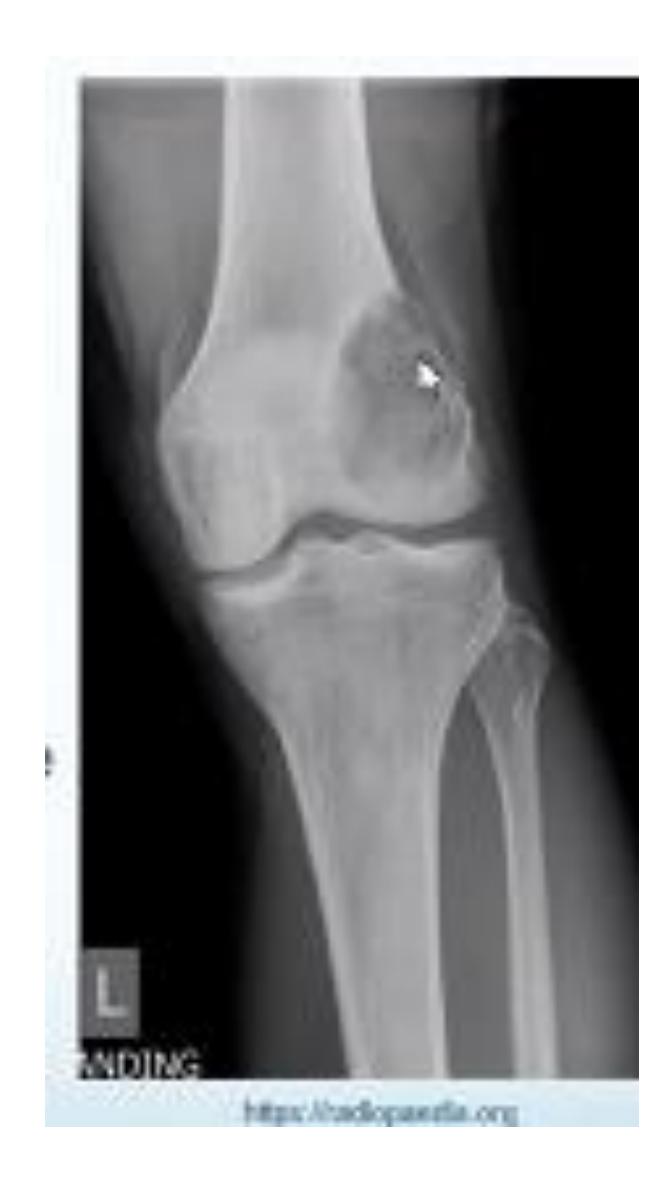

Non-Ossifying Fibroma

What does this picture show?

- A- Non-ossifying fibroma

Clinical Features:

- Found in children

- Incidentally discovered

- Asymptomatic

- Cortical defect